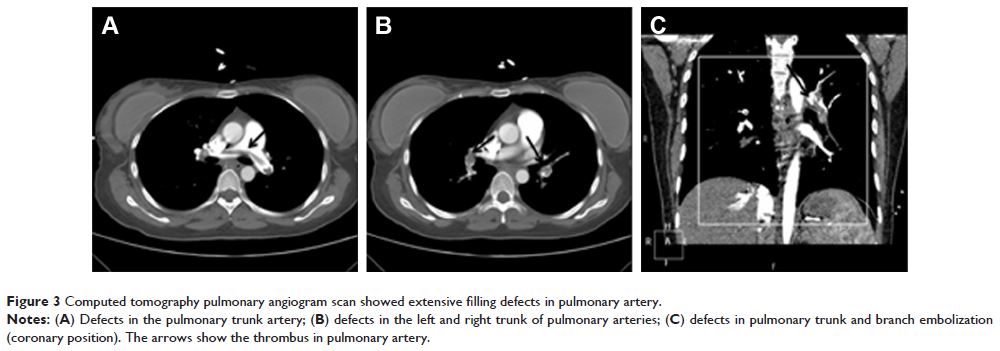

- 作者:Xiaoping Ouyang, Yumin Huang, Xing Jin, Wei Zhao, Tao Hu, Feng Wu, Jianan Huang

- 期刊:OncoTargets and Therapy